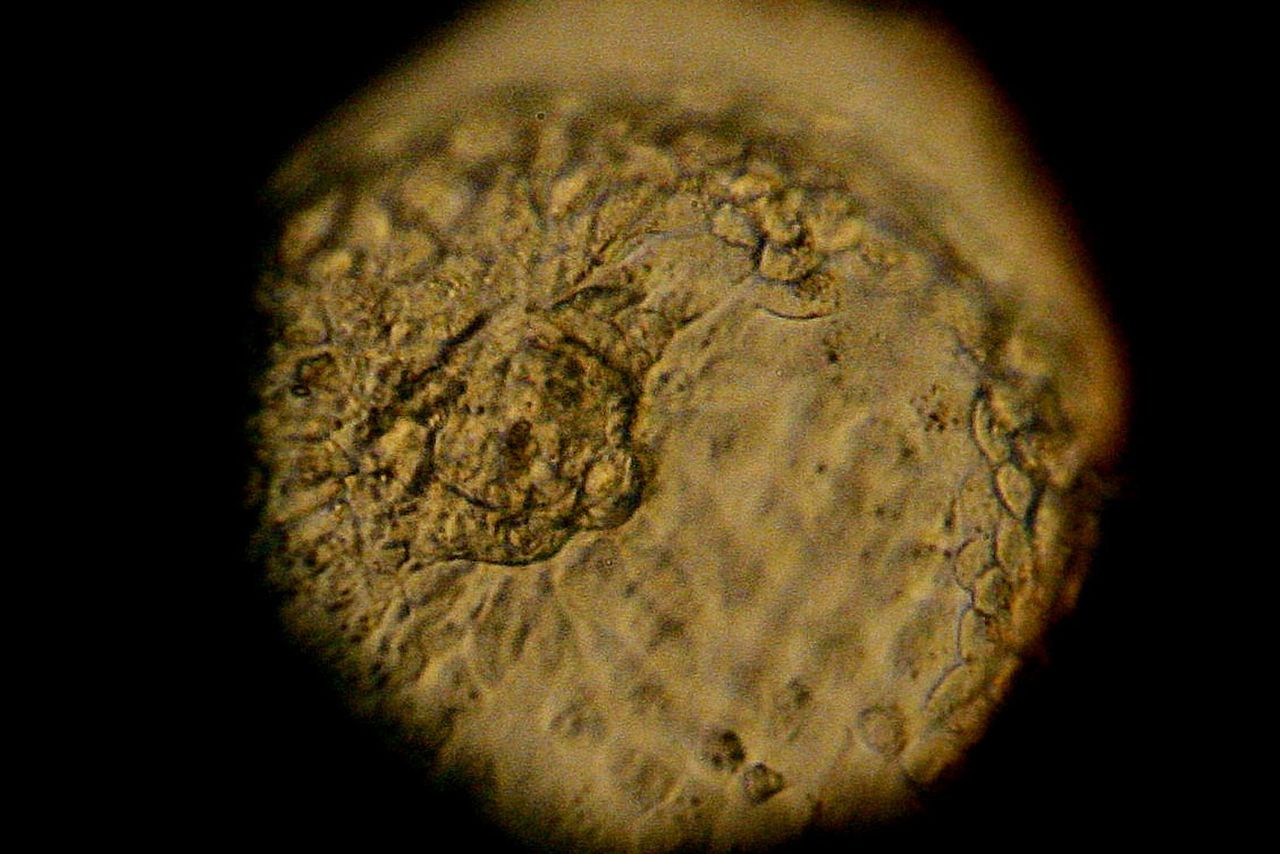

Ученые их Китая сообщили о модифицировании генома эмбриона человека. Это уже вторая попытка китайцев. Первая была осуществлена в прошлом году — тогда специалисты попытались извлечь ген, который отвечает за появление редкого заболевания крови. Как уже сообщалось на Geektimes, команде исследователей из Университета Сунь Ятсена в Гуанчжоу удалось заменить «дефектный» участок ДНК, который и приводил к развитию серьезного заболевания, на нормальный участок без дефекта. Такого рода изменения могут со временем привести к излечению ряда генетических заболеваний, а также редактировать внешность и ликвидировать гены, которые приводят к недостаткам умственного развития.

На этот раз уже другая команда ученых, из Медицинского университета Гуанчжоу провела похожий опыт. Только гены уже не вырезали, а добавляли. Специалисты попытались встроить в ДНК мутацию, которая позволила бы человеку стать устойчивым к воздействию ВИЧ.